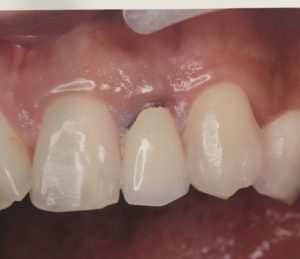

(術後)真ん中の歯がキレイで違和感のないジルコニアセラミックに置き換わっています。今回は、著名な技工士伊藤竜馬先生に仕事をお願いして作成していただいています。

術後では、歯のフィットが良いのは当然だが、術後1週間経過し、ハグキのがセラミックによってきており、より自然なハグキとのつながり感がみられる。ツルツルのセラミックがハグキは大好き!ハグキがむしろよって行きます!

歯肉の炎症や変色もなくなっています。